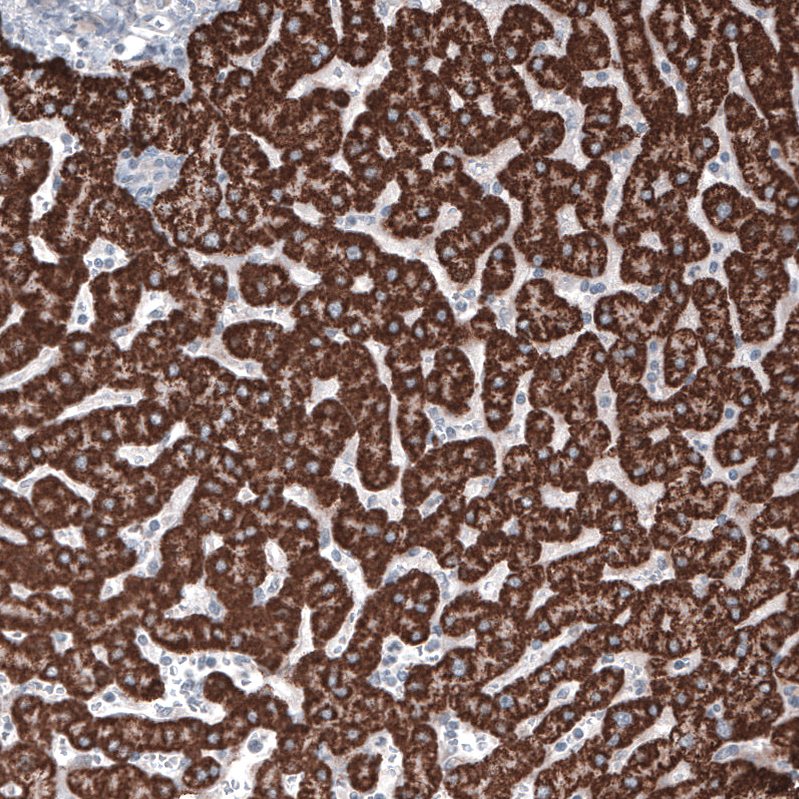

Immunohistochemistry analysis in human liver and tonsil tissues using AMAb91264 antibody. Corresponding OTC RNA-seq data are presented for the same tissues.